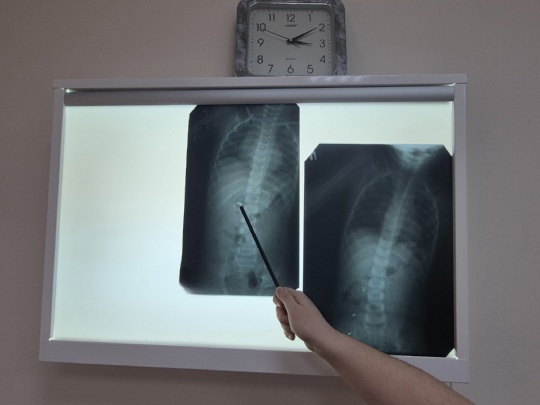

Родители привезли ребенка в Хвалынскую больницу для проведения рентгеновского исследования. Обследование выявило наличие постороннего предмета в желудке маленького пациента. После этого его направили в Балаковскую клиническую больницу (БГКБ) для дальнейшего лечения.

Контрольный рентгеновский снимок показал, что инородное тело состоит из трех частей и что они уже не находятся в желудке, а равномерно распределились по кишечнику.